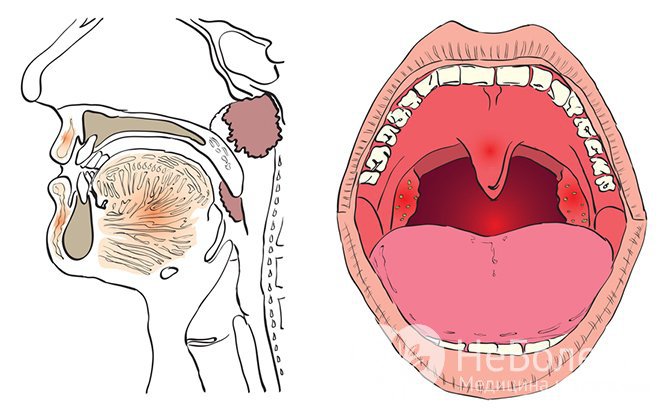

При хроническом тонзиллите воспалительный процесс локализуется в миндалинах

При хроническом тонзиллите воспалительный процесс локализуется в миндалинахЧто такое хронический тонзиллит? Он представляет собой инфекционно-аллергическое заболевание, при котором воспалительный процесс локализуется в области одной или нескольких миндалин. В большинстве случаев происходит поражение небных миндалин, реже затрагиваются боковые валики задней стенки глотки или язычная миндалина.